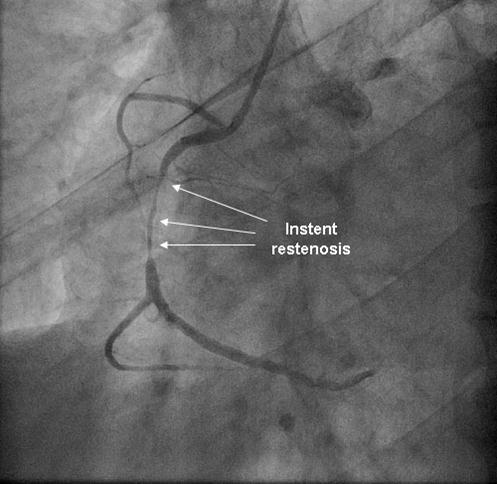

Coronary angiography was again performed. On injections into the left system, collaterals to the distal RCA were demonstrated (figure 1), arising from the left circumflex coronary artery (CX). Injections into the RCA demonstrated tight in-stent restenosis, (figure 2) and a drug eluting stent was successfully implanted. After the angioplasty, injections into the RCA were seen to retrogradely fill the CX (figure 3). The suspicion arose that maybe the left coronary artery had been inadvertently damaged during angiography, so the left coronary was again cannulated and injections performed, demonstrating entirely normal left main and CX arteries. However, the collateral flow that had previously been demonstrated from the CX to the RCA was no longer apparent. On review of the previous angiogram, it was noted that the RCA retrogradely filled the CX despite the original significant stenosis (figure 4). In essence, it became apparent that the bidirectional filling of the RCA from the CX and vice versa was in fact a direct continuity between the vessels and not collaterals, as free flow was noted from the RCA to the CX even when both arteries were completely patent.

Figure 2.Instent restenosis in proximal RCA